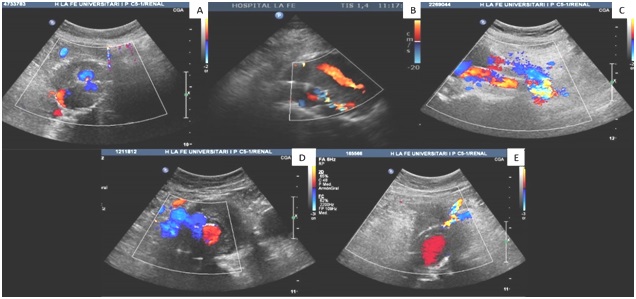

Fig. 5. Imagen A: Endofuga tipo II (arteria mesentérica inferior). Imagen B: Endofuga tipo IA.

La mayoría de las endofugas (65,5%) fueron de tipo II, seguidas de tipo IB (10%) y IA y III (7%), respectivamente (Fig. 6). En todos los casos, hubo un crecimiento medio 0,79 cm + DE 0,31 cm del saco aneurismático, produciéndose una muerte por rotura del mismo debido a una endofuga tipo II (arteria lumbar) de alta presión.

Fig. 6: Imagen A: Endofuga tipo II (arteria lumbar). Imagen B: Endofuga tipo II (arteria mesentérica inferior).

Imagen C: Endofuga tipo IB. Imagen D: Endofuga tipo IA. Imagen E: Endofuga tipo III.